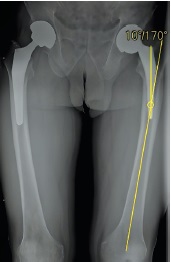

Sequential X-ray methods of research using plain pelvic radiography in the antero-posterior view revealed a satisfactory inclination of the acetabular component, a varus position of the femoral component of 10°, and a distortion of the endoprosthesis contours in the lower region of the acetabular component and the femoral neck component, which was regarded as a fracture of the ceramic liner or head that make up the bearings. Signs of a previously installed DHS surgical hardware, as well as channels from previously inserted cortical and dynamic screws, were visualized in the cortical area in the upper third of the diaphysis of the left femoral bone after removal in the diaphyseal and subtrochanteric regions (Fig. 1, 2).

Fig. 2. Overview X-ray of the hip joints with full femoral capture. On the left is a 10° varus placement of the femoral component